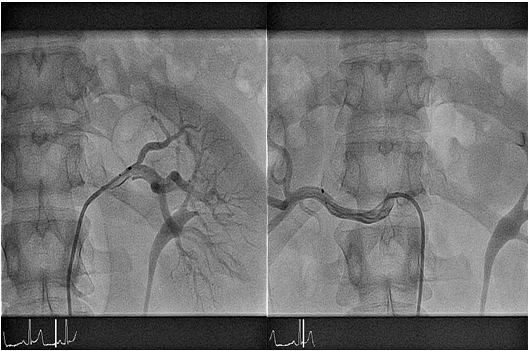

Η νέα μέθοδος

Η εισαγωγή του ασθενούς περιλαμβάνει νοσηλεία μίας ημέρας. Μετά τον κλινικό έλεγχο ο ασθενής υποβάλλεται σε υπερηχογράφημα νεφρών και triplex νεφρικών αρτηριών προς αποκλεισμό στενώσεως νεφρικής αρτηρίας. Η επέμβαση διενεργείται στο Αιμοδυναμικό Εργαστήριο.  Yπό τοπική αναισθησία παρακεντείται η μηριαία αρτηρία και απεικονίζονται οι νεφρικές αρτηρίες. Ακολουθεί εισαγωγή στη νεφρική αρτηρία καθετήρα απονεύρωσης (Simplicity, Medronic) ο οποίος είναι συνδεδεμένος εξωτερικά με τη γεννήτρια της κατάλυσης.  Χορηγούνται σε έξι θέσεις στο αγγείο, στα σημεία που μετρηθούν αντιστάσεις μεγαλύτερες από 250 Ohm, συνεδρίες υψίσυχνου εναλλασόμενου ρεύματος έως 8 Watts διάρκειας  120 δευτερολέπτων η καθεμία. Η πρώτη θέση χορηγήσεως είναι στο άπω τμήμα της νεφρικής αρτηρίας και διαδοχικά ο καθετήρας αποσύρεται κατά 5 mm και στρέφεται κατά 90 μοίρες προς την επόμενη θέση.  Η ίδια διαδικασία επαναλαμβάνεται και στην άλλη νεφρική αρτηρία. Μετά την ολοκλήρωση της πράξεως αφαιρείται ο καθετήρας  από τη μηριαία αρτηρία και ο ασθενής μεταφέρεται στο δωμάτιο του κινητοποιούμενος μετά από λίγες ώρες.  Εξέρχεται της κλινικής την επομένη.

Στο Αιμοδυναμικό Εργαστήριο της Ευρωκλινικής  Αθηνών εφαρμόσθηκε το Σεπτέμβριο 2011 για πρώτη φορά στην Ελλάδα από τους ιατρούς της 1ης Καρδιολογικής Κλινικής η συγκεκριμένη μέθοδος. Από τότε έχει εφαρμοσθεί σε δεκάδες ασθενείς με πολύ καλά αποτελέσματα η συγκεκριμένη μέθοδος. Όλοι οι ασθενείς πληρούσαν τις απαραίτητες ενδείξεις για να υποβληθούν σε απονεύρωση των νεφρικών αρτηριών. Η επέμβαση ολοκληρώθηκε σε όλους με επιτυχία αν και σε ορισμένους παρατηρήθηκε παροδικά σπασμός της νεφρικής αρτηρίας, ο οποίος λύθηκε με χορήγηση νιτρωδών εντός αυτής.  Οι ασθενείς παρουσίασαν τους επόμενους μήνες σταδιακή πτώση της πιέσεως (από 169/96 mmHg κατά μέσο όρο πριν την επέμβαση σε 136/79 mmHg έξι μήνες μετά)  με μείωση των λαμβανομένων φαρμάκων από 3,9±0,8 σε2,9±0,8.

Εικ 1. Νεφρική αγγειογραφία που αναδεικνύει  τον καθετήρα ablation Semlicity  στη αριστερή ( αρ. τμήμα)  και στη δεξιά (δε. τμήμα) νεφρική αρτηρία.